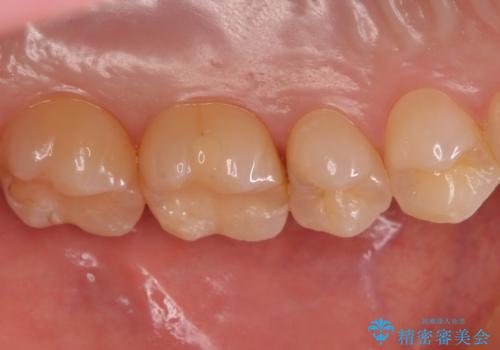

歯と歯の間の虫歯 セラミックインレーでの治療

- 検査の結果、歯と歯の間に虫歯が見つかった患者様です。

白く目立たないものでの治療をご希望されたため、セラミックインレーでの治療となりました。

歯と歯の間は虫歯の好発部位です。

適合の良いセラミックインレーで修復することで見た目の綺麗さを保ったまま治療することができます。